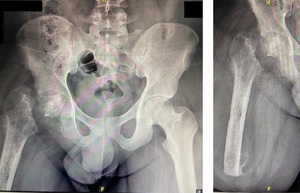

The first-stage revision surgery was performed in December 2021. Preoperative radiographs (Figure 6) revealed an AVN of the right femoral head, nonunion of the femoral neck, and osteopenia of the proximal femur. Surgical procedures included debridement of the AKA stump and removal of the native femoral head, followed by the insertion of an antibiotic-loaded cement spacer. Postoperative cultures again identified Enterobacter cloacae, necessitating a six-week course of intravenous Meropenem. A postoperative radiograph (Figure 7) showed the placement of an articulated antibiotic-loaded cement spacer. By February 2022, after a two-week antibiotic-free period, the patient’s CRP level had decreased to 18.2 mg/L. Hip aspiration performed in June 2022 showed a further decrease in CRP to 10.2 mg/L, with negative cultures.